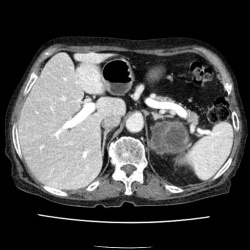

Мужчина. 60 лет. Поступал в клинику с якобы левосторонней почечной коликой. УЗИсты дают двусторонний гидронефроз и камень в н\трети правого мочеточника. Проведена обзорная и в\в урография. Ваше...

Пациент направлен на внутривенную урографию. Диагноз - "Мочекаменная болезнь?". Врач УЗИ сообщил, что "камни" с обеих сторон. По поводу картины сильно не распространялся.

Внутривенная урография. Пациент направлен из военкомата.Жалоб пациент не предъявляет. Произведено стандартное исследование.